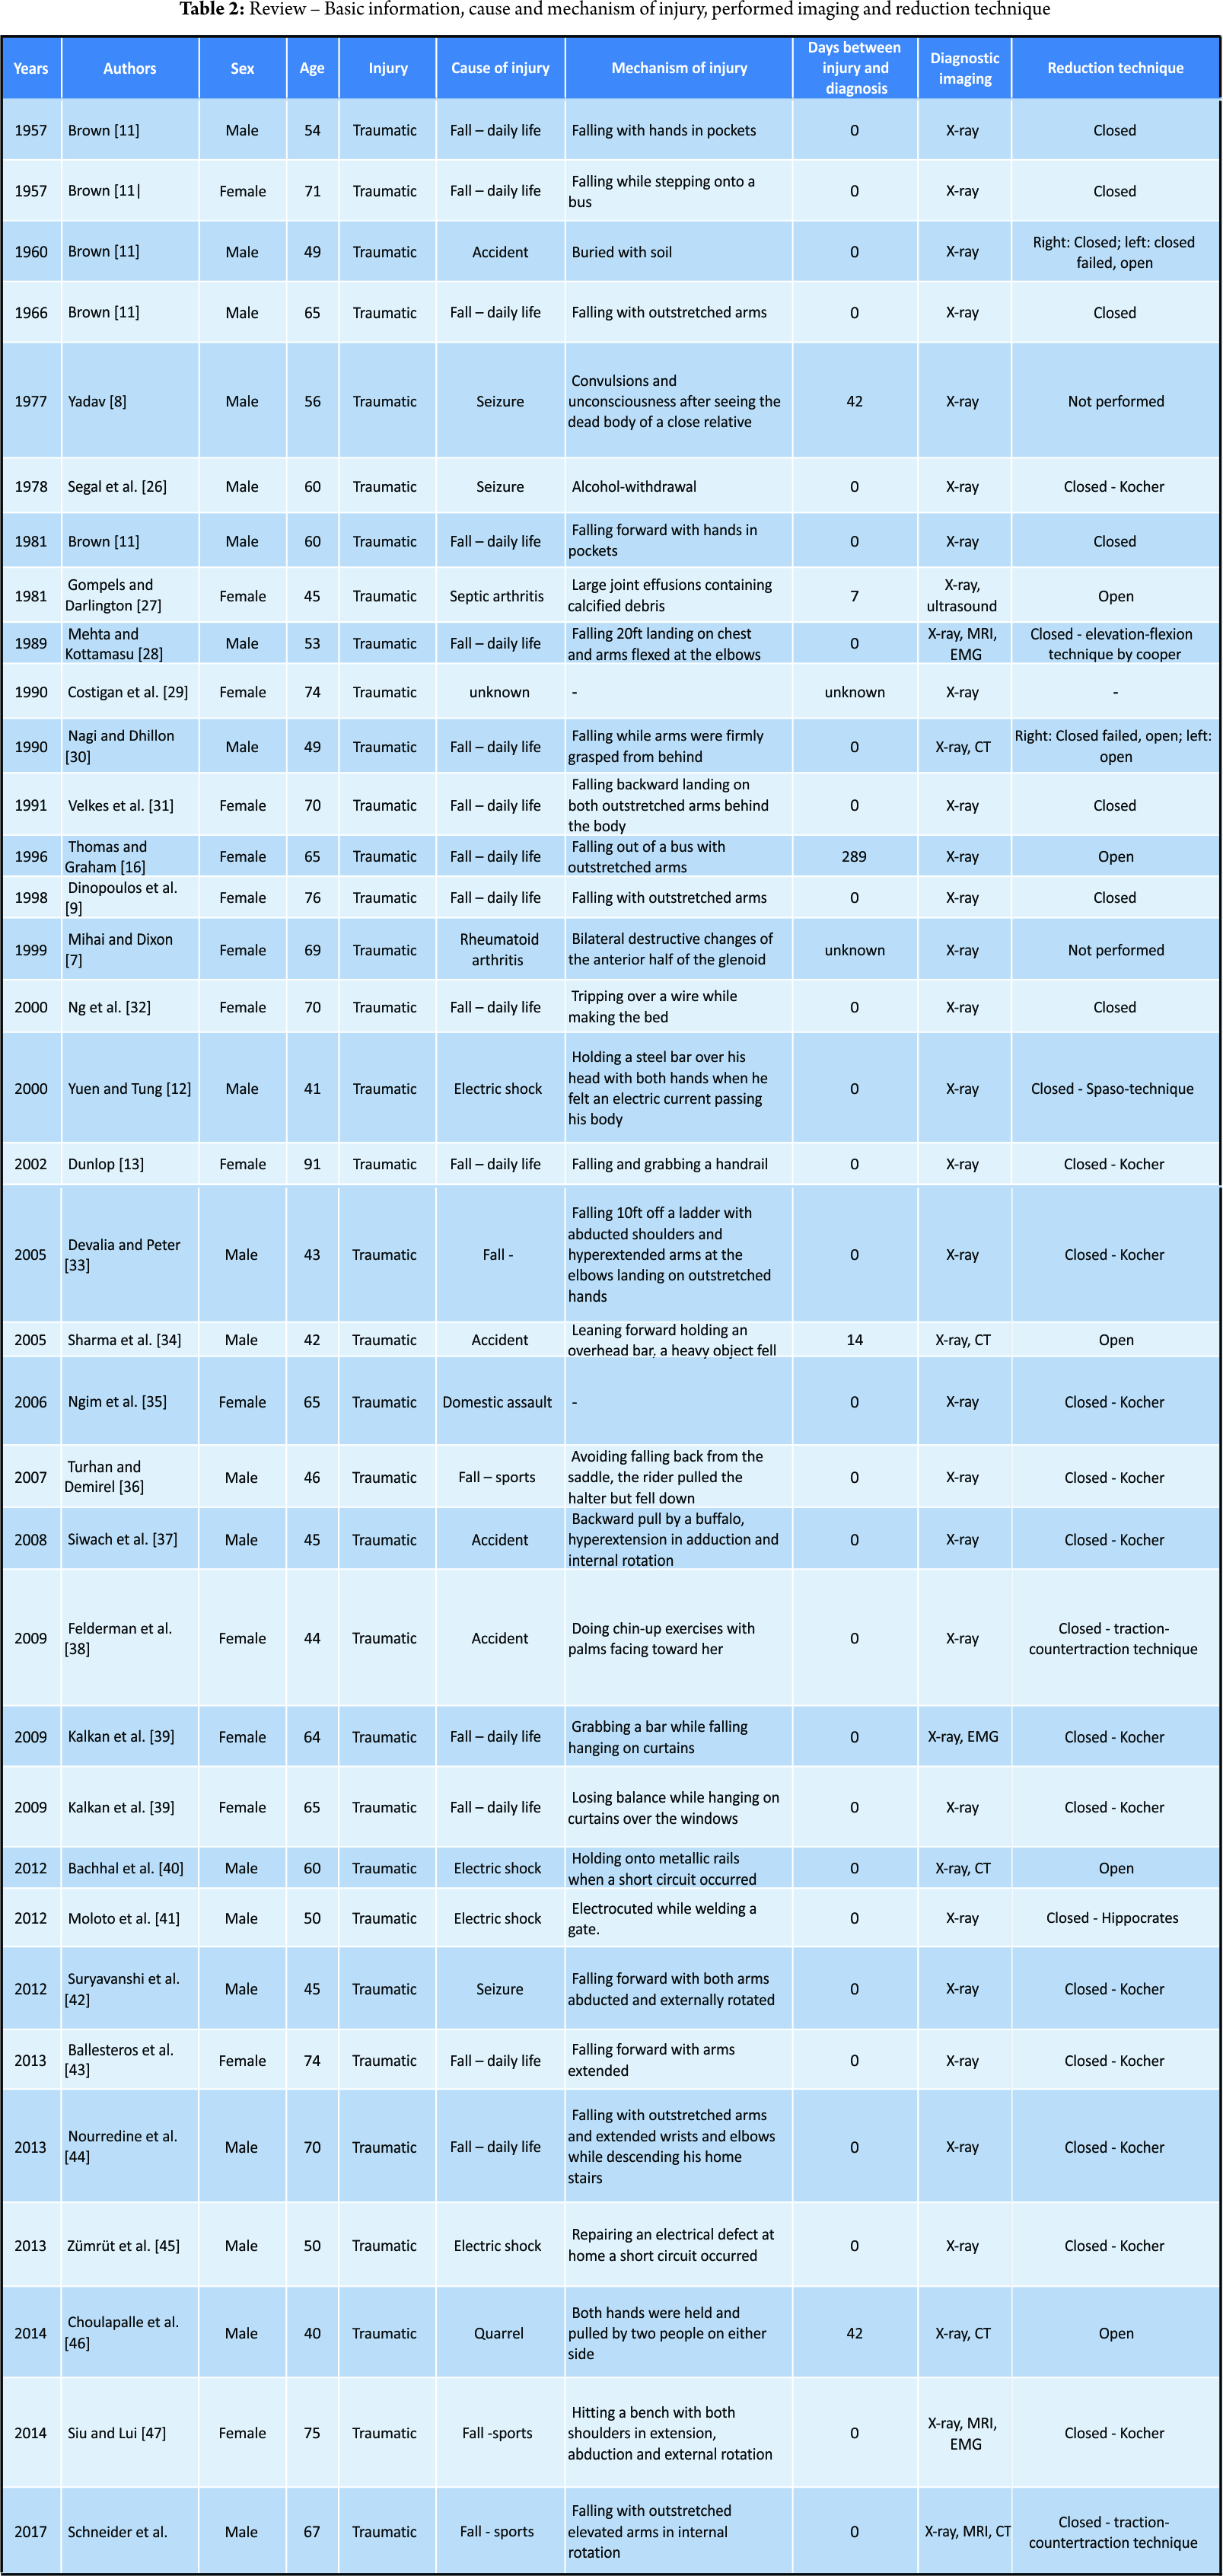

Including this case (see “case report” above), we identified and analyzed 35 case reports regarding 20 male and 15 female patients with an average age of 58.9 years (female: 59.2 years, male: 58.6 years) (Tables 2 and 3).

Diagnostics

Thirty reported cases were traumatic, four cases atraumatic, and the reason for injury in one case remains unclear. Out of the 30 traumatic cases, 19 were due to a fall in everyday life, four cases due to an accident, four cases involved electric shocks and two patients due to assault. The four reported atraumatic cases were in two cases due to chronic arthritis (×1 septic arthritis, ×1 rheumatoid arthritis) and in addition two cases due to a seizure without any related fall or brunt.

Imaging

In all 35 cases, an X-ray examination was used to assess the shoulder joint pre- and post-reduction. A CT-scan for further fracture evaluation was performed in three cases. An MRI scan was performed in three and ultrasound imaging in one case. An EMG was also conducted in three reported cases.

Concomitant injuries

A total of 19 patients suffered a concomitant fracture of the proximal humerus (×8 bilateral, ×11 unilateral) ranging from a simple fracture of the greater tuberosity to a four-part humeral head fracture. Concomitant soft-tissue damage was discovered in nine patients with seven reported cases of rotator cuff tears (×2 bilateral, ×5 unilateral), two Hill–Sachs lesions, two Pulley-lesions, and six reported cases of injured nerves.

Reduction-technique

In 26 cases a closed reduction was performed (×13 Kocher technique, ×2 traction-counteraction technique, ×1 Hippocrates technique, ×1 Cooper technique, ×1 Spaso technique, and ×8 not specified), in four cases open reduction was performed, in two cases a bilateral closed reduction failed unilaterally and was subsequently performed in an open approach. In another two cases, no reduction was performed as the situations were chronic and an initial reduction unpromising [7, 8].